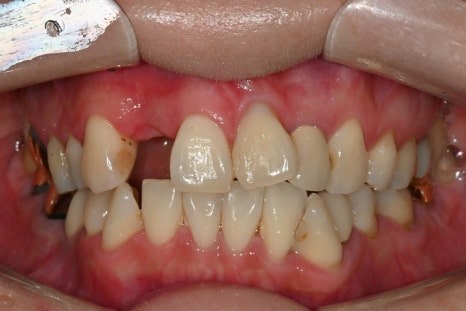

치료 전

치료 후

위와 같이 앞니 임플란트 치료를

잘 마친 환자분께서

위 환자분은 부러진 앞니를

발치하고 임플란트를 즉시 식립했으며

디지털 방식으로 제작한

임시치아를 당일에 끼워드렸던 분으로,

당일 제작한 디지털 임시치아

전체 치료기간이 2개월이 채 걸리지 않아

매우 만족하시고

많은 분들을 소개해주신 분이었습니다.